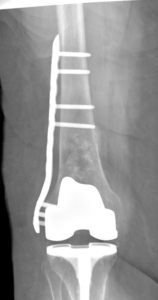

Distal femur fractures and tibial plateau fractures cause a disruption in the weight bearing surfaces of the knee joint. The distal femur and the tibial plateau are covered with a smooth surface called articular cartilage, which allows these bones to glide over each other during normal daily activities such as walking, climbing stairs, etc. A break in this surface can predispose a person to developing arthritis in the knee joint. These fractures are commonly fixed with plates and screws that hold the bones in place through the healing process. These fractures most often require a period of no weight bearing on the affected leg while the bones are healing.

Knee fracture (distal femur, patella, and tibial plateau fractures)